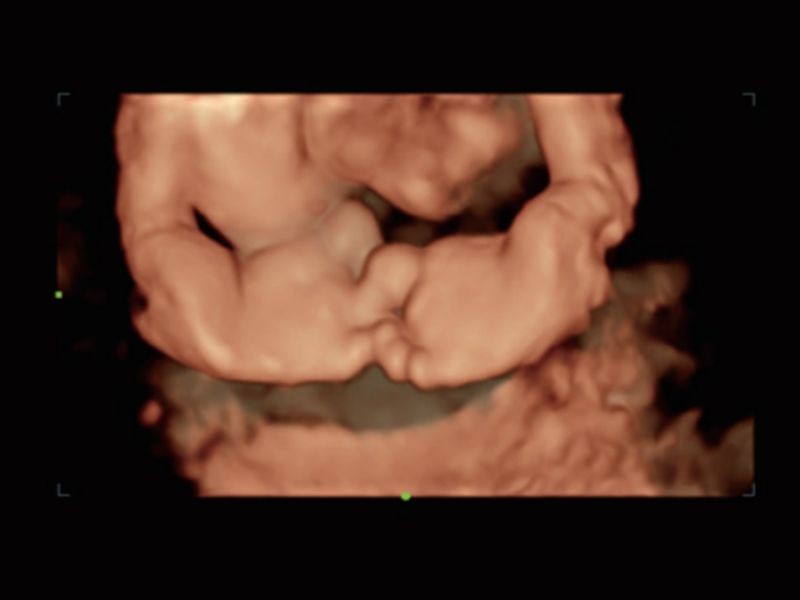

Realismo e clareza sem precedentes - iLive com Hyaline

Ao imitar múltiplas fontes de luz de intensidade variável, o iLive ajuda a melhorar significativamente a resolução anatômica detalhada tanto para estruturas superficiais quanto internas por meio de renderização de volume de alta velocidade.